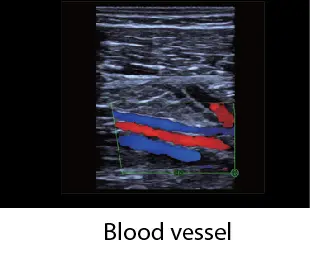

Различни режими на визуализация: B-mode, M-mode, Color Doppler, Power Doppler, PW Doppler

B-режим, М-режим, цветен доплер, Power доплер и PW доплер

| Честоти в Цветен режим: | линеен: 4.0, 4.4, 5.0 MHz; конвексен: 2.5, 2.8, 3.3 MHz; |

| Честоти в PW | линеен: 4.0, 4.4, 5.0 MHz; конвексен: 2.5, 2.8, 3.3 MHz; |